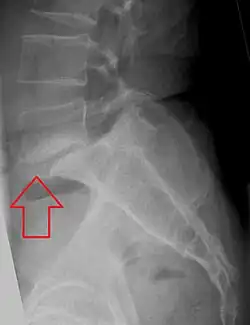

Espondilolistese

Espondilolistese é o deslocamento anterior de uma vértebra ou da coluna vertebral em relação à vertebra inferior[1][2], ou, mais geralmente, em qualquer direção. [3][4]